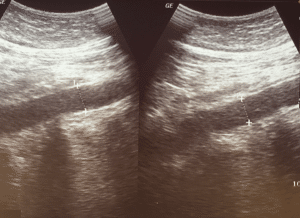

1-Abdominal aortic aneurysmÂ

Vascular ultrasound of abdominal aortaÂ

AAA Overview: Symptomatic AAA, particularly with a hemodynamic instability is a medical emergency that requires prompt intervention. While physical examination may miss an AAA, but bedside ultrasound has a high sensitivity (94% to 100%) in detecting an aneurysm.Â

Urgency in Diagnosis: Ultrasound cannot reliably detect aneurysm rupture. However, the presence of AAA in a hemodynamically compromised patient needs immediate surgical consultation.Â

Step-by-Step Examination Technique:Â

Transverse Views:Â

Coverage Area: Visualize the abdominal aorta from the xiphoid process to the iliac bifurcation. Start scanning from just below the sternum down to umbilicus.Â

Measurement: In the transverse plane, when measured from the outer wall to the outer wall in the anterior-posterior direction. An aorta larger than 3.0 cm is typically classified as aneurysm.Â

Iliac Artery Examination: Evaluate the common iliac arteries for aneurysms with diameter >1.5 cm after scanning the aorta.Â

Longitudinal Views:Â

Maximizing Accuracy: Ensure the widest diameter of aorta is captured, and avoid false negatives by scanning laterally through the vessel.Â

Rare Forms: Saccular aneurysms are although rare, but best seen in the longitudinal views.Â